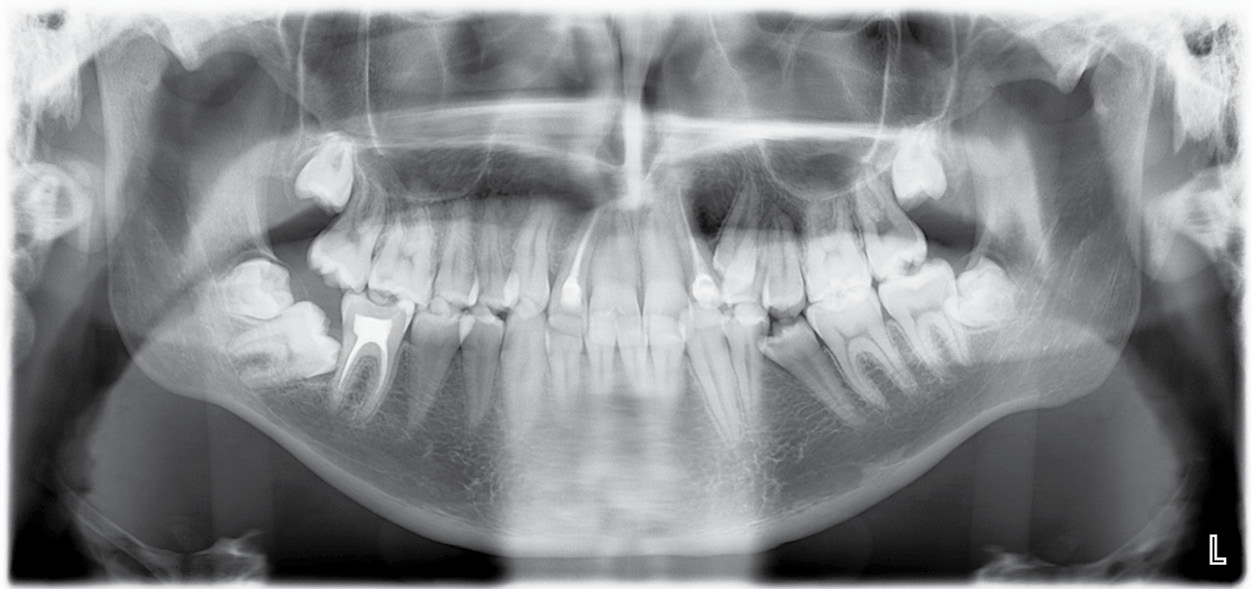

Результаты проведенного клинического обследования позволяют сделать вывод о наличии у пациента зубочелюстно-лицевой аномалии. На ортопантомограмме пациента выявлено наличие 32 постоянных зубов, зубы 1.8, 2.8, 3.8, 4.7, 4.8 находятся в ретенции (рис. 3). Для уточнения проведена ТРГ головы пациента в боковой проекции. Анализ ТРГ в боковой проекции в программе Dolphin Imaging (рис. 4) позволил поставить предварительный диагноз — дистальная окклюзия, гнатическая форма.

Рис. 3. Ортопантомограмма пациента П., 15 лет / Fig. 3. Panoramic image of patient P., 15 years old